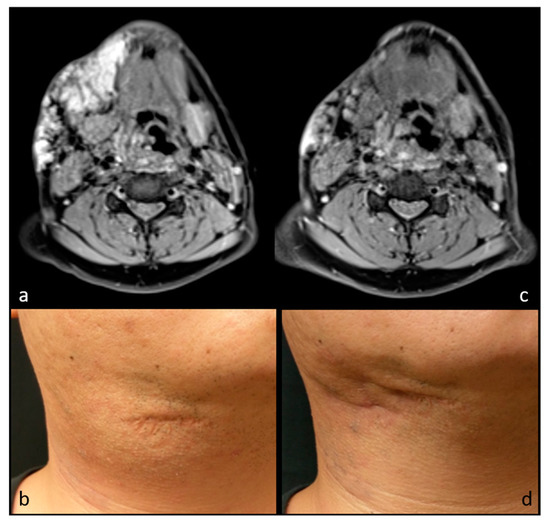

| 6 | 16 | F | Neurofibroma | Left temporal fossa | US, MR | 13.2 | 1.1 | 17 | 91.7% | 3 | 1 | GA | 4 |

| 7 | 5 | F | Neurofibroma | Right temporal fossa | US, MR | 14.9 | 4.1 | 28 | 72.5% | 3 | 1 | GA | 1 |